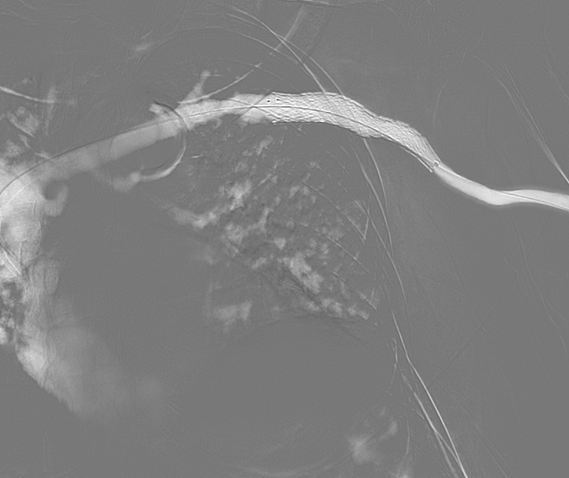

투석혈관 협착,

스텐트삽입술

시술 전

시술 후